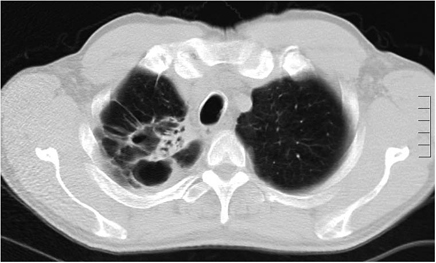

Klinisch zijn longinfecties door NTM zijn nauwelijks te onderscheiden van longtuberculose, hoewel het beloop doorgaans trager is. Van de twee radiologische te onderscheiden varianten van NTM-longinfecties is de holtevormende in Nederland veruit het meest frequent. Afwijkingen op longfoto’s en CT-scans zijn niet betrouwbaar te onderscheiden van longtuberculose (foto 1,2). De tweede radiologische variant, gekenmerkt door bronchiëctasieën en nodulaire afwijkingen in lingula en middenkwab (foto 3), is zeldzamer in Nederland. Mogelijk is het feit dat deze afwijkingen door NTM veroorzaakt kunnen worden nog niet erg bekend in Nederland; in de Verenigde Staten is deze ziektevorm veelvoor-komend, veel meer dan de klassieke holtevormende variant.

Foto 3: Nodulair-bronchiectatische longinfectie door m.intracellulare